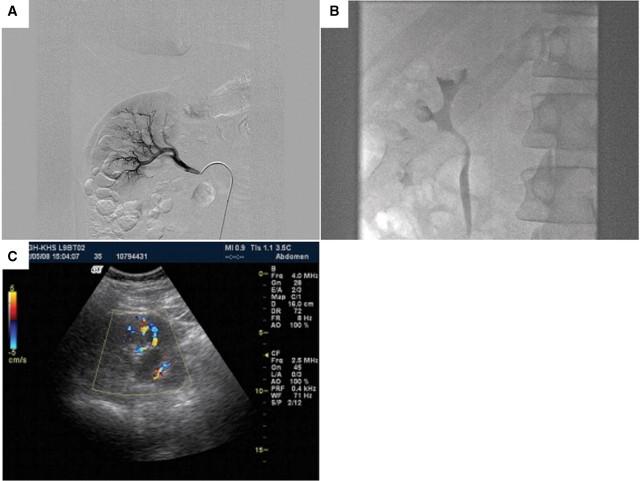

Spontaneously resolving large intrarenal artery aneurysm-a case report.

https://cdn.ncbi.nlm.nih.gov/pmc/blobs/9324/4421391/d2ea4820854a/sfp086fig1.jpg